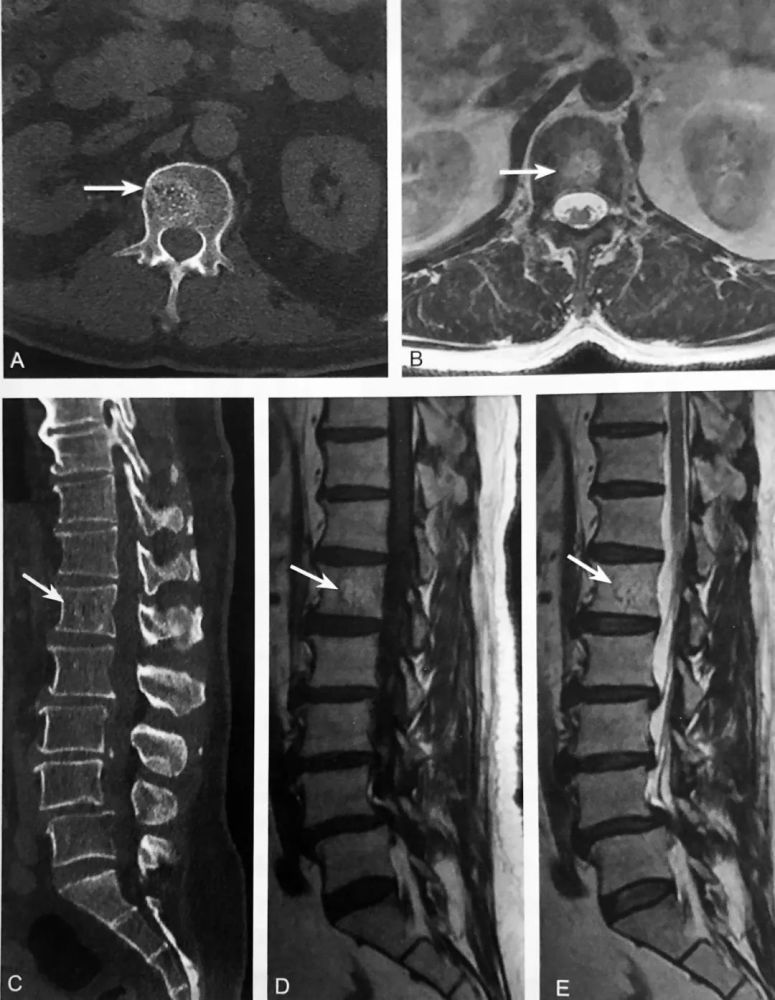

骨样骨瘤,患者的并发症有持续性剧痛,夜间的时候,症状最明显

图片尺寸1024x776